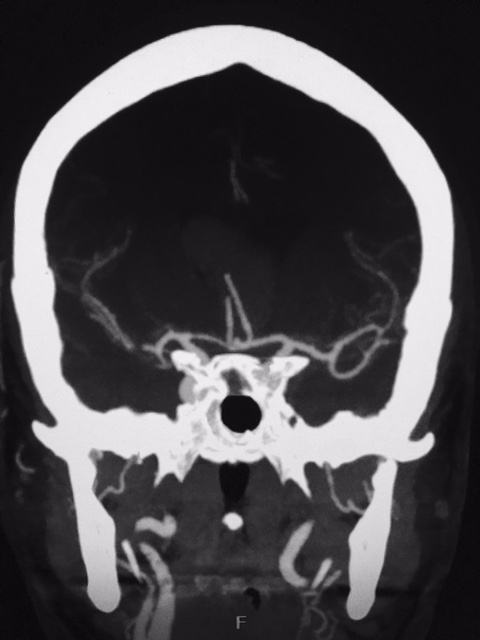

Aneurisma de topo da carótida

SNA. 76 anos . Durante investigação ambulatorial de cefaléia e tremor nas mãos foi realizado Angiotomografia de crânio evidenciando aneurisma incidental em topo da...